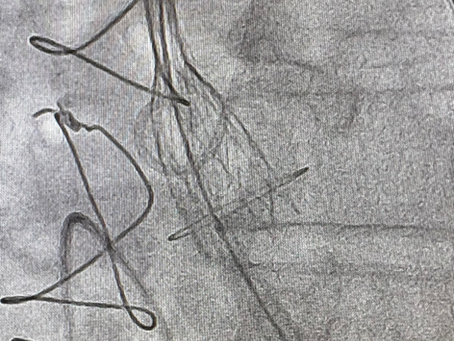

💓 “Valve-in-Valve”: uma nova chance para o coração bater com mais força

A medicina cardiovascular vive uma verdadeira revolução — e uma das técnicas mais modernas é o “Valve-in-Valve” , um procedimento que devolve qualidade de vida a pacientes que já passaram por uma ou mais cirurgias cardíacas. 🔍 O que é o procedimento Valve-in-Valve? O termo em inglês significa literalmente “ válvula dentro de válvula ”.Ele é utilizado quando uma prótese valvar (biológica) implantada em uma cirurgia anterior começa a apresentar desgaste ou mau funcionamento

Cateterismo x Angioplastia: você sabe a diferença?

Quando o assunto é coração, muitos pacientes se confundem ao ouvir os termos cateterismo cardíaco e angioplastia coronária . Apesar de...

Você sabia que um stent coronário pode voltar a obstruir e precisar de novo tratamento?

O stent coronário é um dos maiores avanços da cardiologia moderna. Ele funciona como uma “mola” que mantém a artéria aberta após uma...